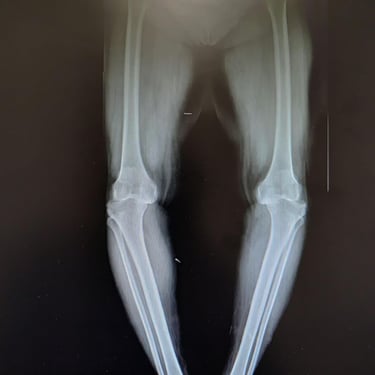

Total knee replacement and partial knee replacement

Trauma (Fractures)

Orthopedic trauma (fractures) refers to injuries to the musculoskeletal system, like bones, joints, and muscles, often from accidents, falls, or sports